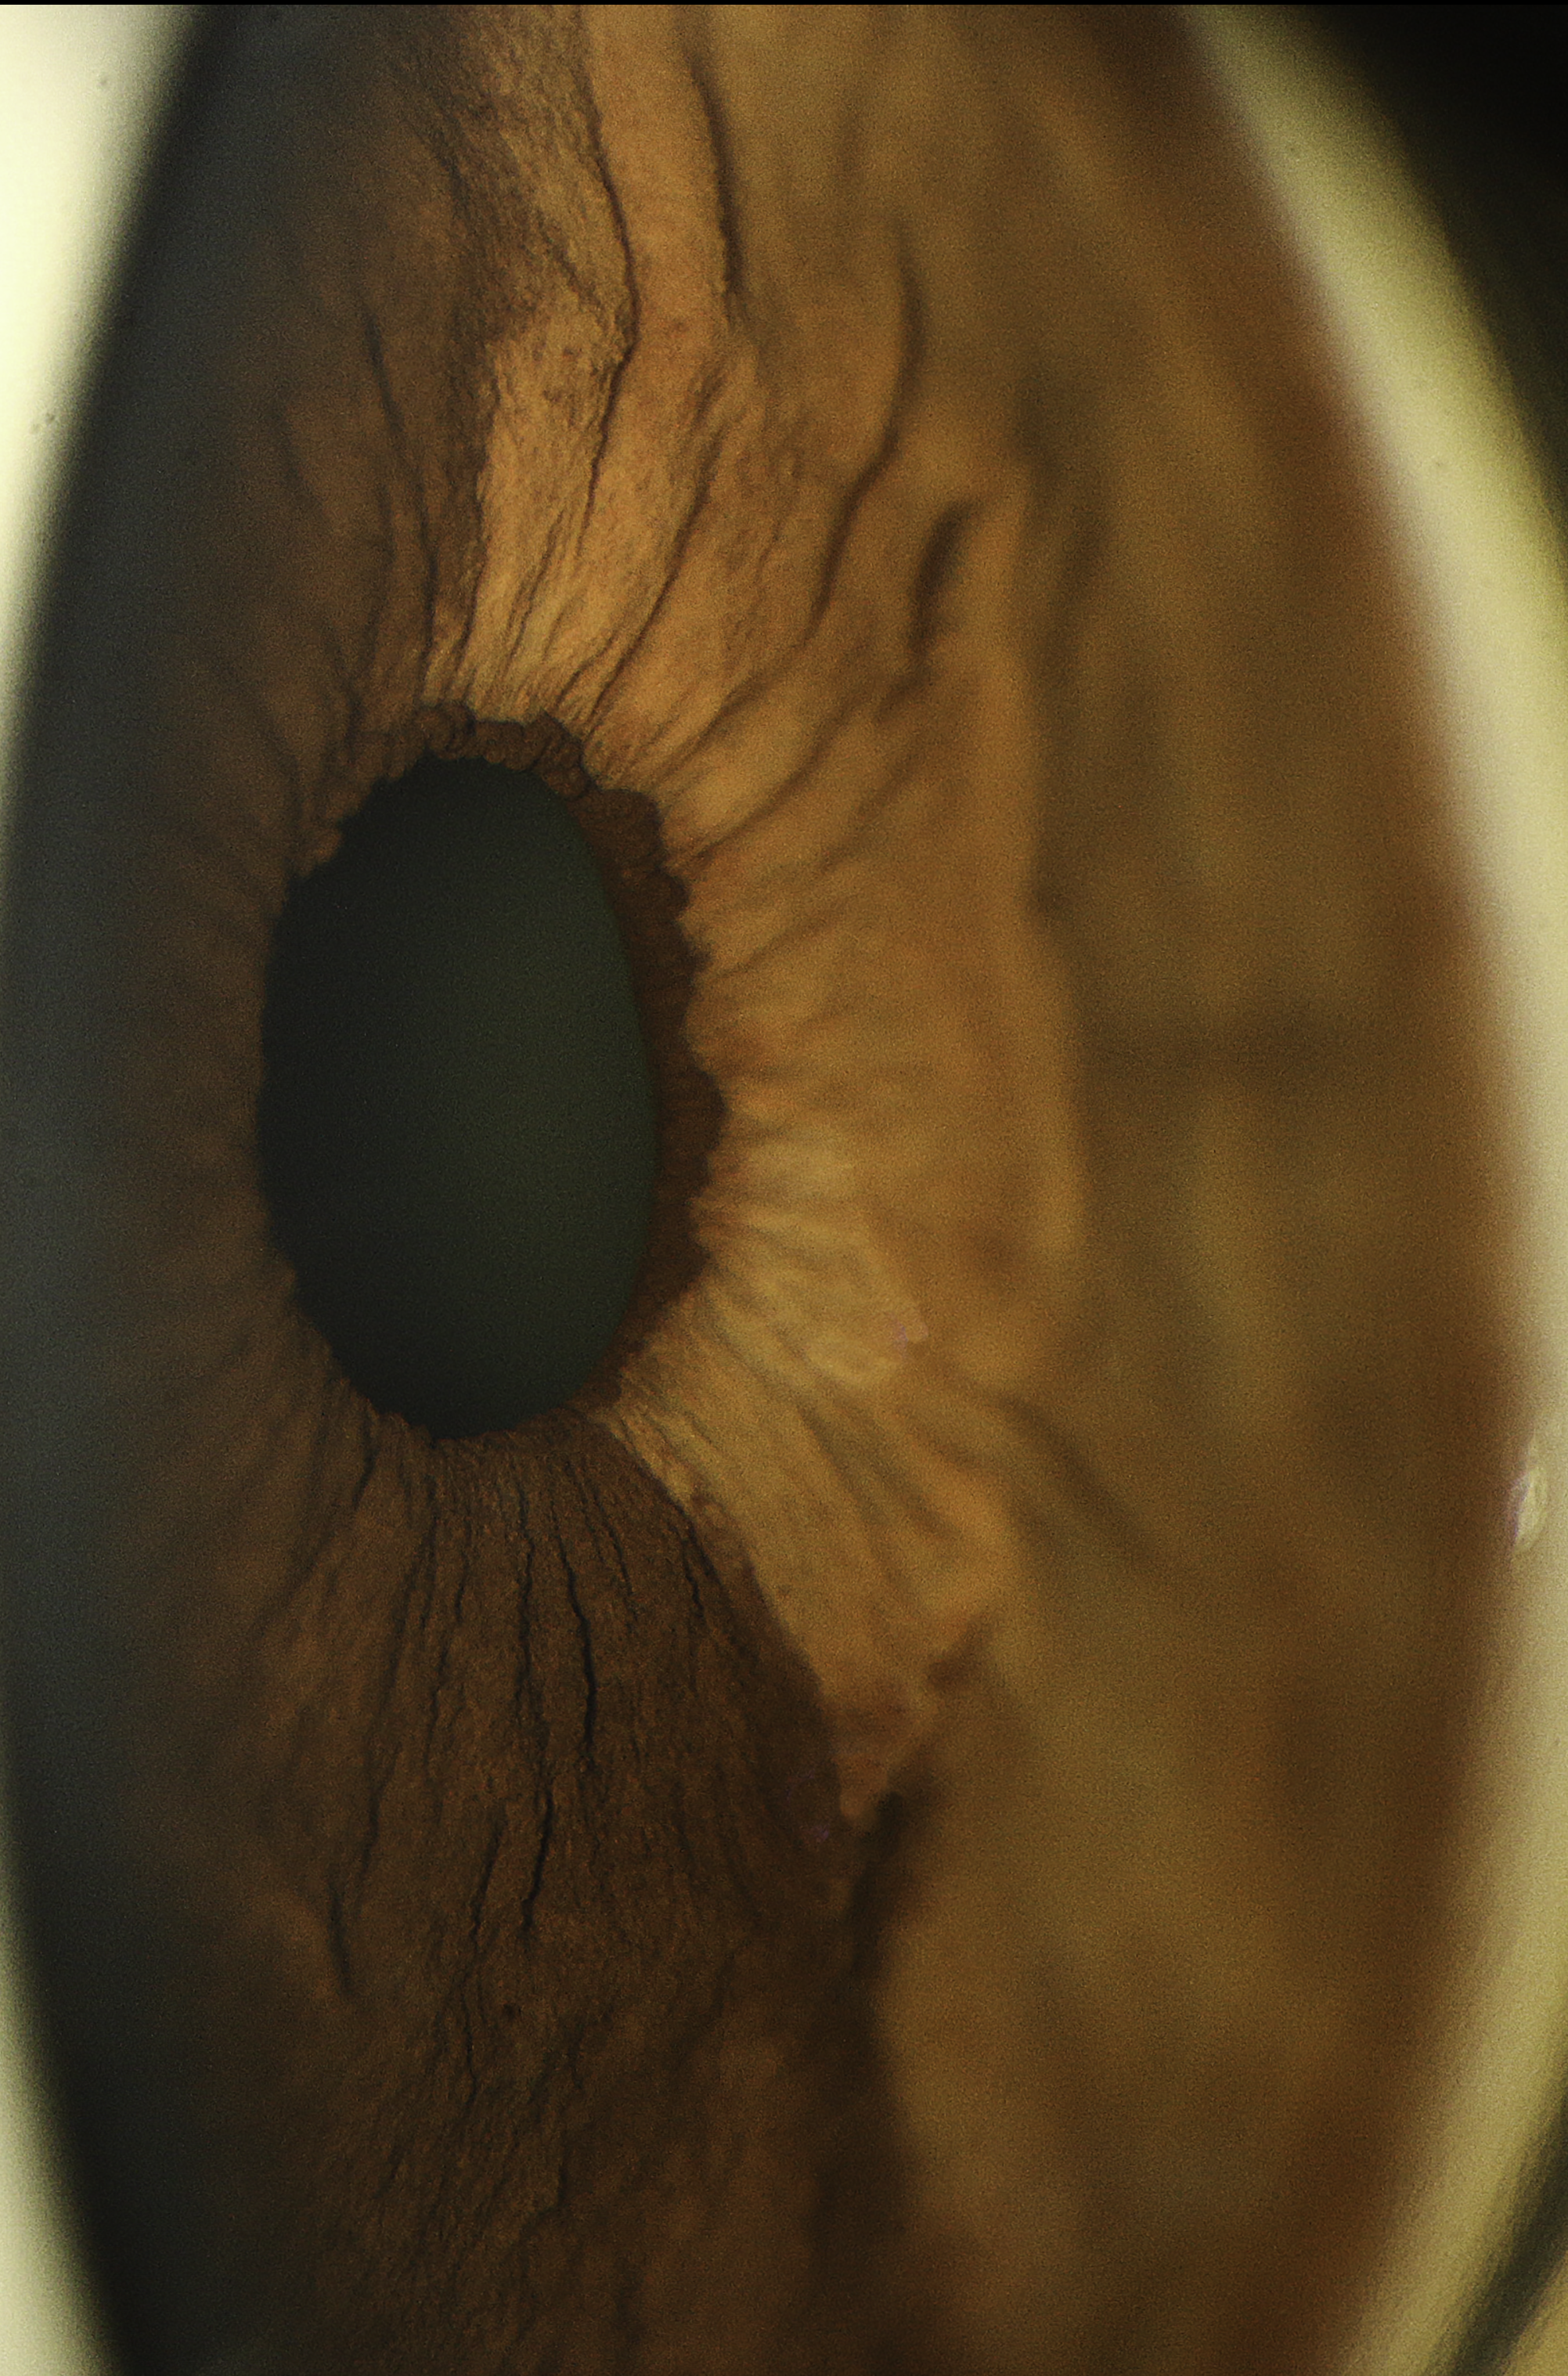

Heterochromia of Iris Presented by Judith Gulian, OCT-C This photograph received Third Place, Gonio Photography in the 2025 OPS Scientific Exhibit. Filed Under Cornea OPS Photo